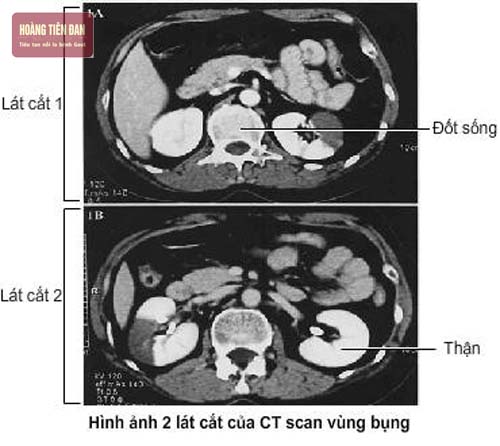

- Chụp CT đường tiết niệu: so với chụp X quang thì phương pháp chẩn đoán sỏi thận này tiên tiến hơn. Nó vừa có thể chẩn đoán được sỏi thận vừa phát hiện được các rối loạn khác có thể dẫn đến các triệu chứng như bệnh sỏi thận.

- Phương pháp chụp CT scan xoắn ốc không cản quang: là cách chẩn đoán sỏi thận thường sử dụng nhất nhằm mục đích phát hiện sỏi hoặc muốn xác định tình trạng tắc nghẽn đường tiểu. Ưu điểm của phương pháp này đó là không cần phải tiêm cản quang, tạo sự an toàn, chẩn đoán hiệu quả hơn IVP trong trường hợp sỏi thận hay đường tiểu.

Chụp CT giúp chẩn đoán sỏi thận.